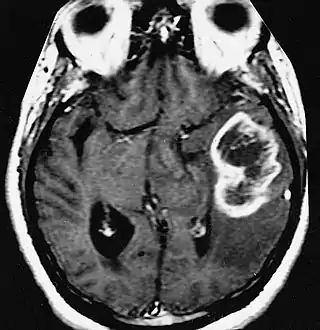

Diagnóstico por imagen y glioblastoma

La TC muestra una lesión de morfología irregular, predominantemente hipodensa y fuertemente dishomogénea, debido a la presencia de grandes áreas necróticas de más clara hipodensidad y de áreas sólidas hiperdensas. Estas últimas son la expresión de un rápido crecimiento y por lo tanto de una elevada malignidad. Son frecuentes las zonas hemorrágicas, que van desde pequeños focos a grandes áreas hemáticas que pueden cubrir toda la lesión. Es característica la morfología en "mariposa" si el tumor se asienta en ambos hemisferios a través del cuerpo calloso.

Tras la aplicación de contraste aparecen gruesos anillos alrededor de las áreas necróticas. En la RM, la parte sólida aparece hipointensa en T1 e hiperintensa en T2 con zonas de señal más elevada en las partes de mayor celularidad. Las áreas necróticas, hiperintensas en T2, pueden presentarse hipo-, iso- o hiperintensas en T1 en función del contenido proteico o de productos de la degradación de la hemoglobina. El realce tras el contraste suele ser intenso e irregular en la periferia del tumor e identifica sobre todo la componente celular "proliferativa" de la neoplasia. Son comunes las áreas puntiformes y serpiginosas de ausencia de señal de flujo, asociadas a la presencia de una neovascularización rica. Estos vasos de neoformación patológica carecen de barrera hematoencefálica, lo que explica tanto la abundante impregnación como el edema vasogénico perilesional (véase la sección anterior), debido al paso de líquido al medio extracelular.[71][72]